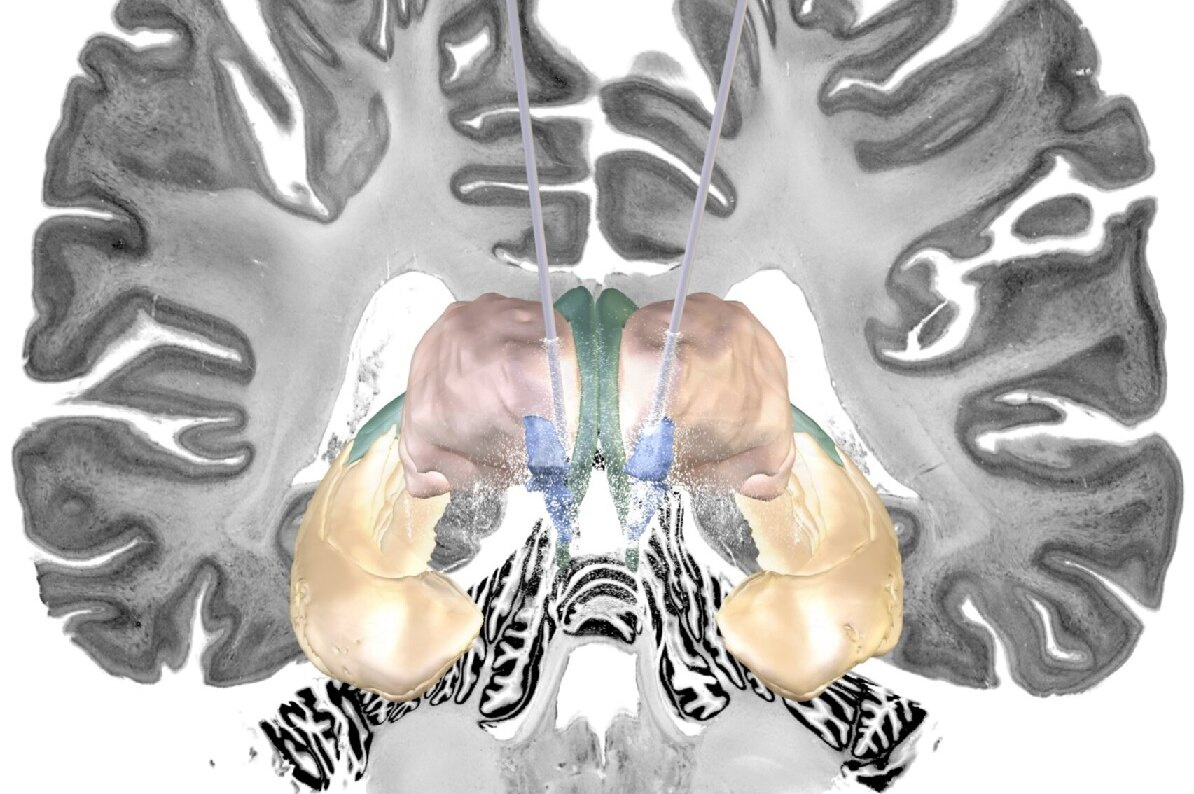

Болезнь Альцгеймера является наиболее распространенной причиной деменции, но ее лечить очень трудно, часто - невозможно. Одной из возможных терапий является глубокая стимуляция мозга с помощью своего рода электростимулятора.

Глубокая стимуляция мозга (DBS) — это форма терапии, которая уже одобрена во многих странах для лечения неврологических двигательных расстройств, таких как болезнь Паркинсона и дистония, а также психоневрологических заболеваний, таких как обсессивно-компульсивное расстройство.